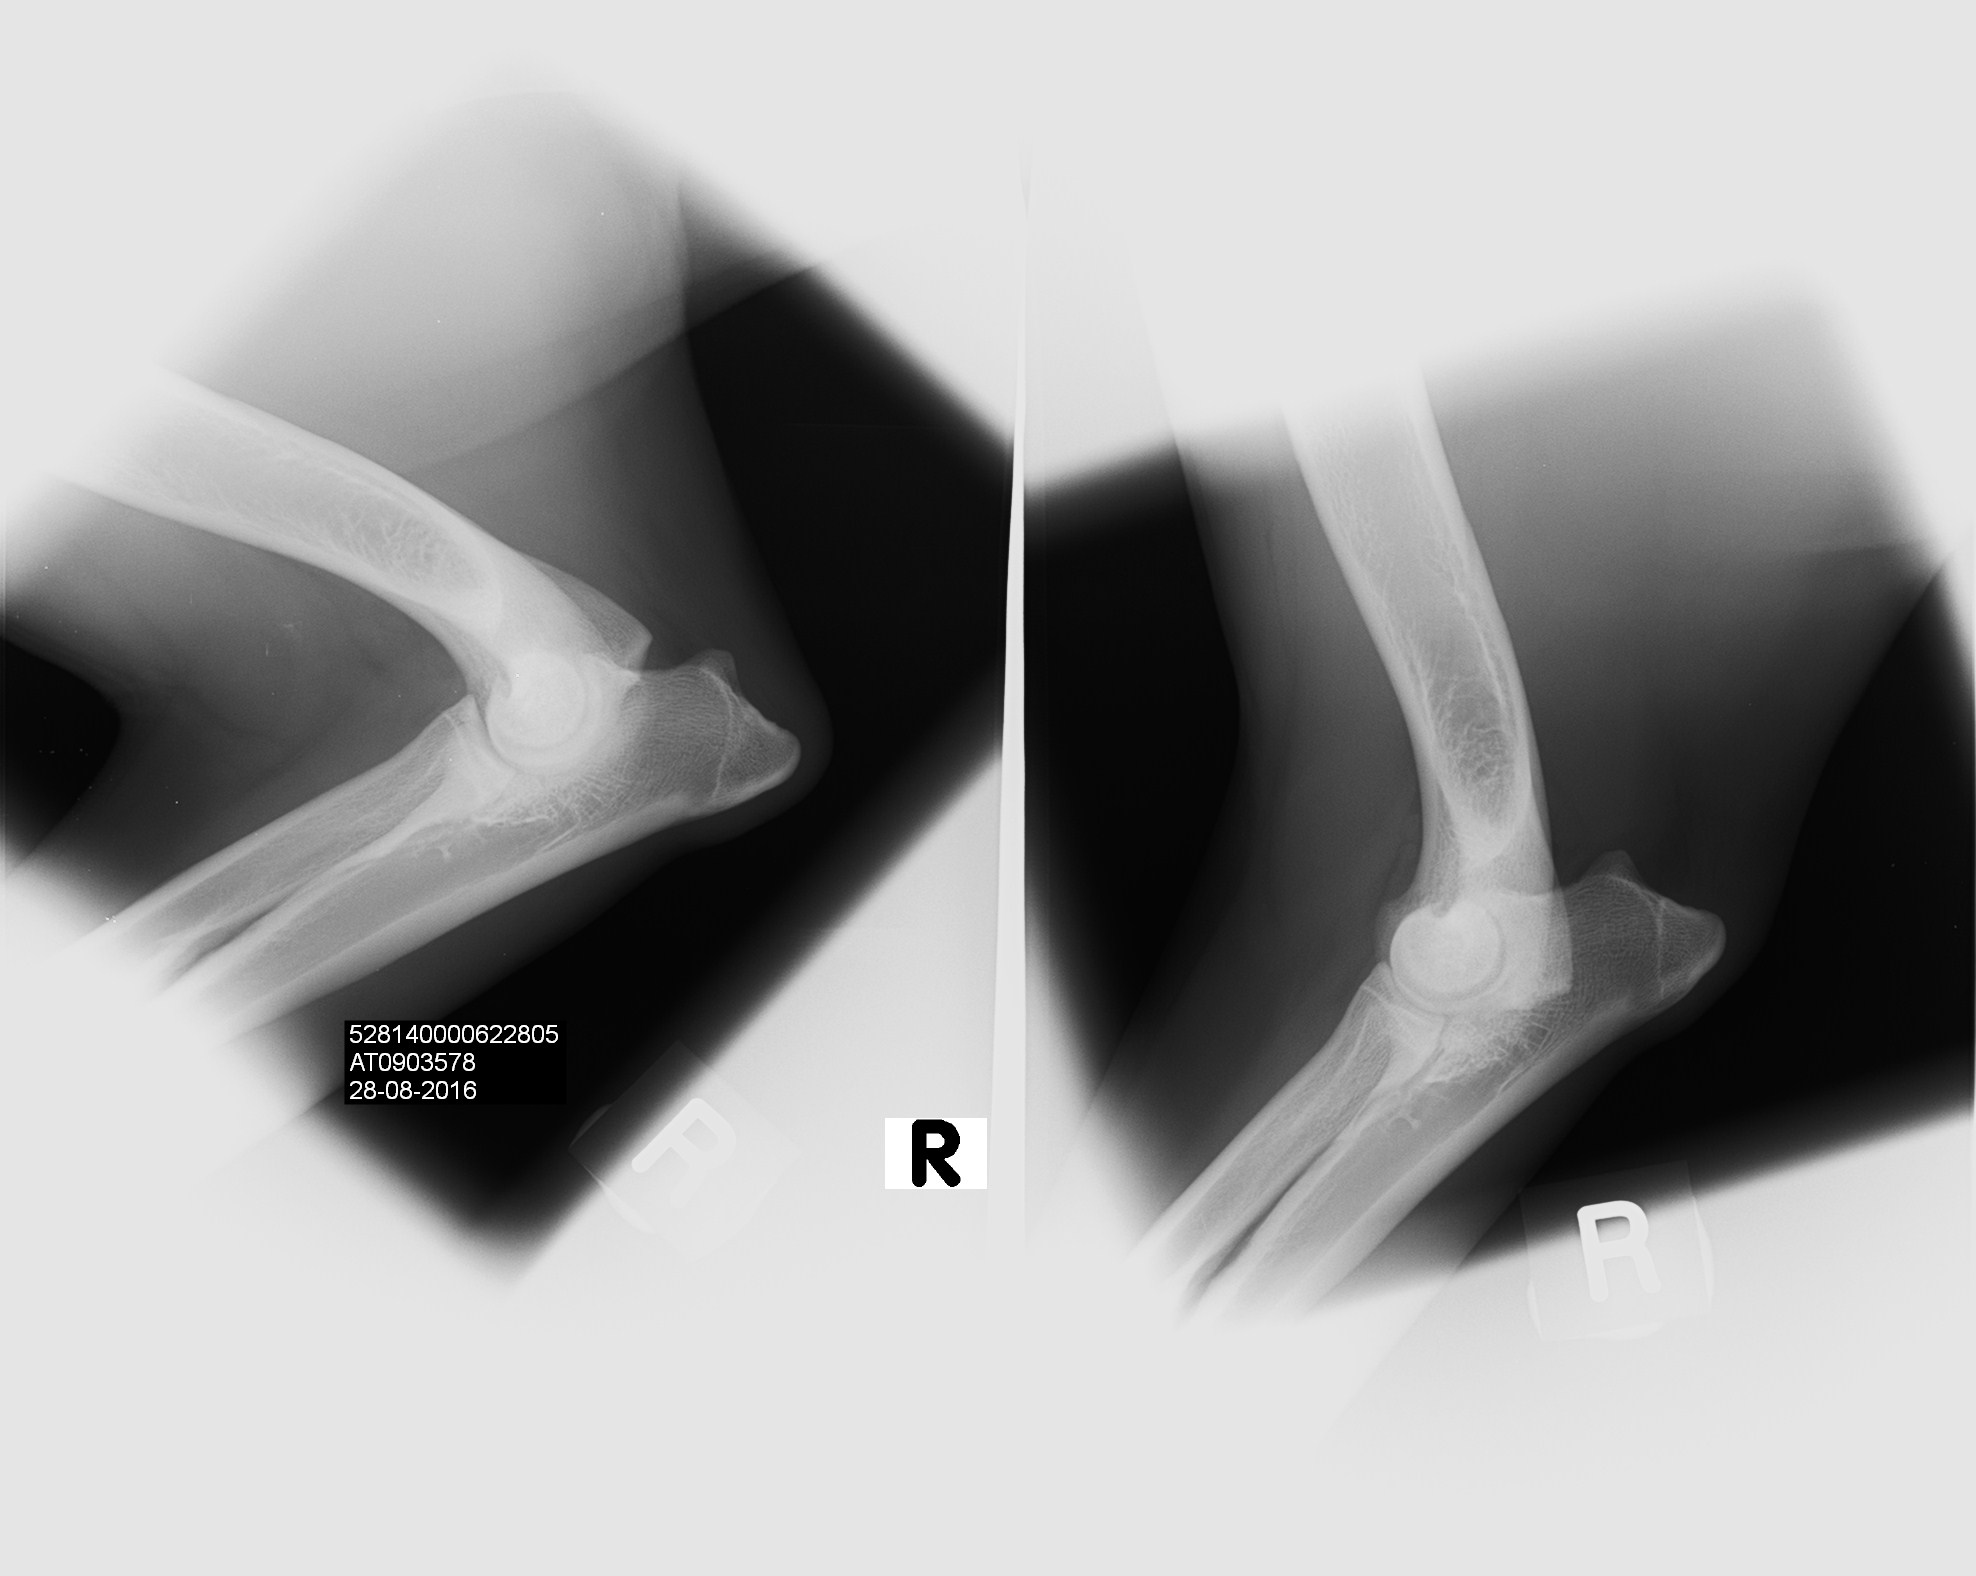

arrack-s-home-xia0002 Published October 14, 2016 at 1976 × 1576 in Xia’s health results are back! ← Previous